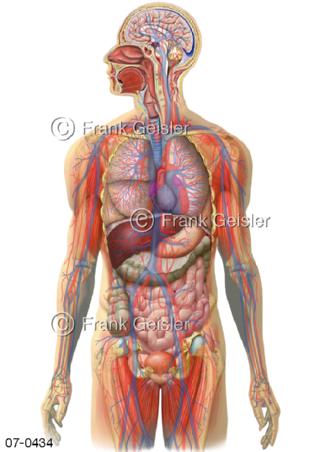

Bildergalerie Herz, Blutkreislauf

Bilder zu Herz, ein muskuläres Hohlorgan, das den menschlichen Körper durch rhythmische Kontraktionen mit Blut versorgt und dadurch die Durchblutung der Organe sichert, das Kreislaufsystem zeigt den Transport von arteriellem sowie venösem Blut durch das kardiovaskuläre System (Herz-Kreislauf-System), bestehend aus Blutgefäßen, Lymphgefäßen und dem Herz